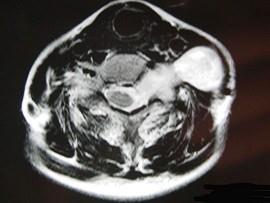

问题 52岁女性患者,左颈部无痛性包块渐进性增大,MRI检查如图,应考虑为 ( )

选项 A、左侧颈部转移癌 B、左侧颈部脂肪瘤 C、左侧颈部神经纤维瘤 D、左侧颈部动脉瘤 E、左侧颈部神经鞘瘤

答案 E